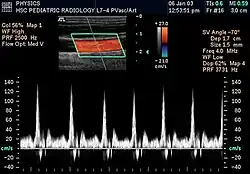

Спектральная доплерография общей каротидной артерии

Потоковая спектральная доплерография (ПСД)

Непрерывная (постоянноволновая) ПСД

Основана на постоянном излучении и постоянном приёме отражённых ультразвуковых волн. При этом величина сдвига частоты отражённого сигнала определяется движением всех структур на пути ультразвукового луча в пределах глубины его проникновения.